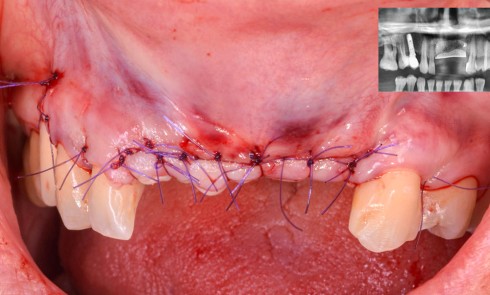

Contexte – Processus de décision La traction des lambeaux, nécessaire pour assurer la fermeture primaire des berges lors des procédures...